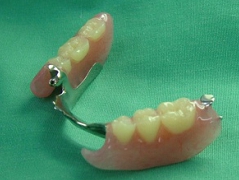

ノンクラスプデンチャーは,

金属のバネが見えないので,見た目が良好です.

(ポリアミド高分子樹脂↓:エステショット使用例)